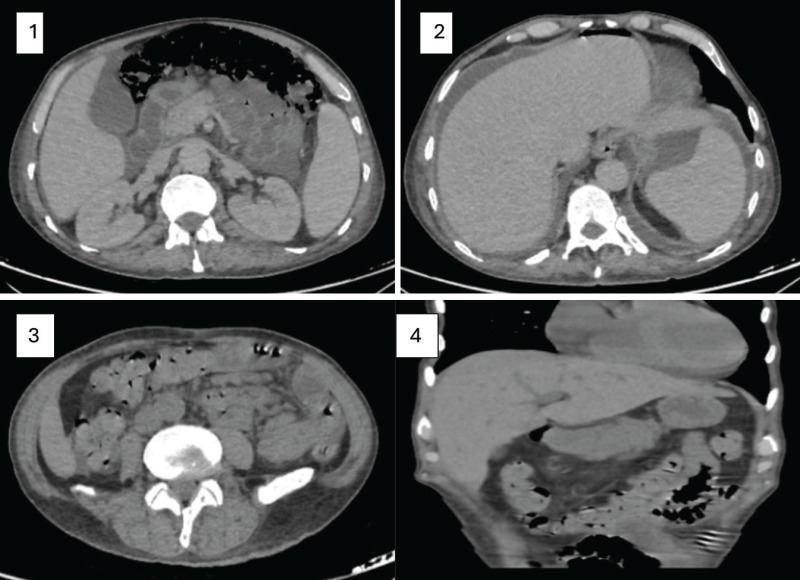

What Happened Suddenly - Acute Abdomen? A Difficult Case of ATRA-Related Pneumatosis Cystoides Intestinalis